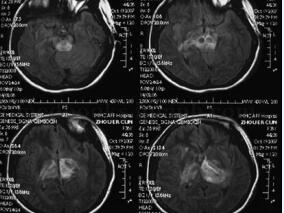

1小时条评论55岁男性,头晕、饮水呛咳、四肢乏力4个月余。头颅MRI提示右侧小脑齿状核陈旧性出血,左侧延髓体积增大。这是何病?该如何治疗? 临床资料 患者男性,55岁,主因头晕、饮水呛咳、四肢乏力4个月余于2008年2月19日入院。于2007年10月出现头晕、饮水呛咳、四肢乏力,...